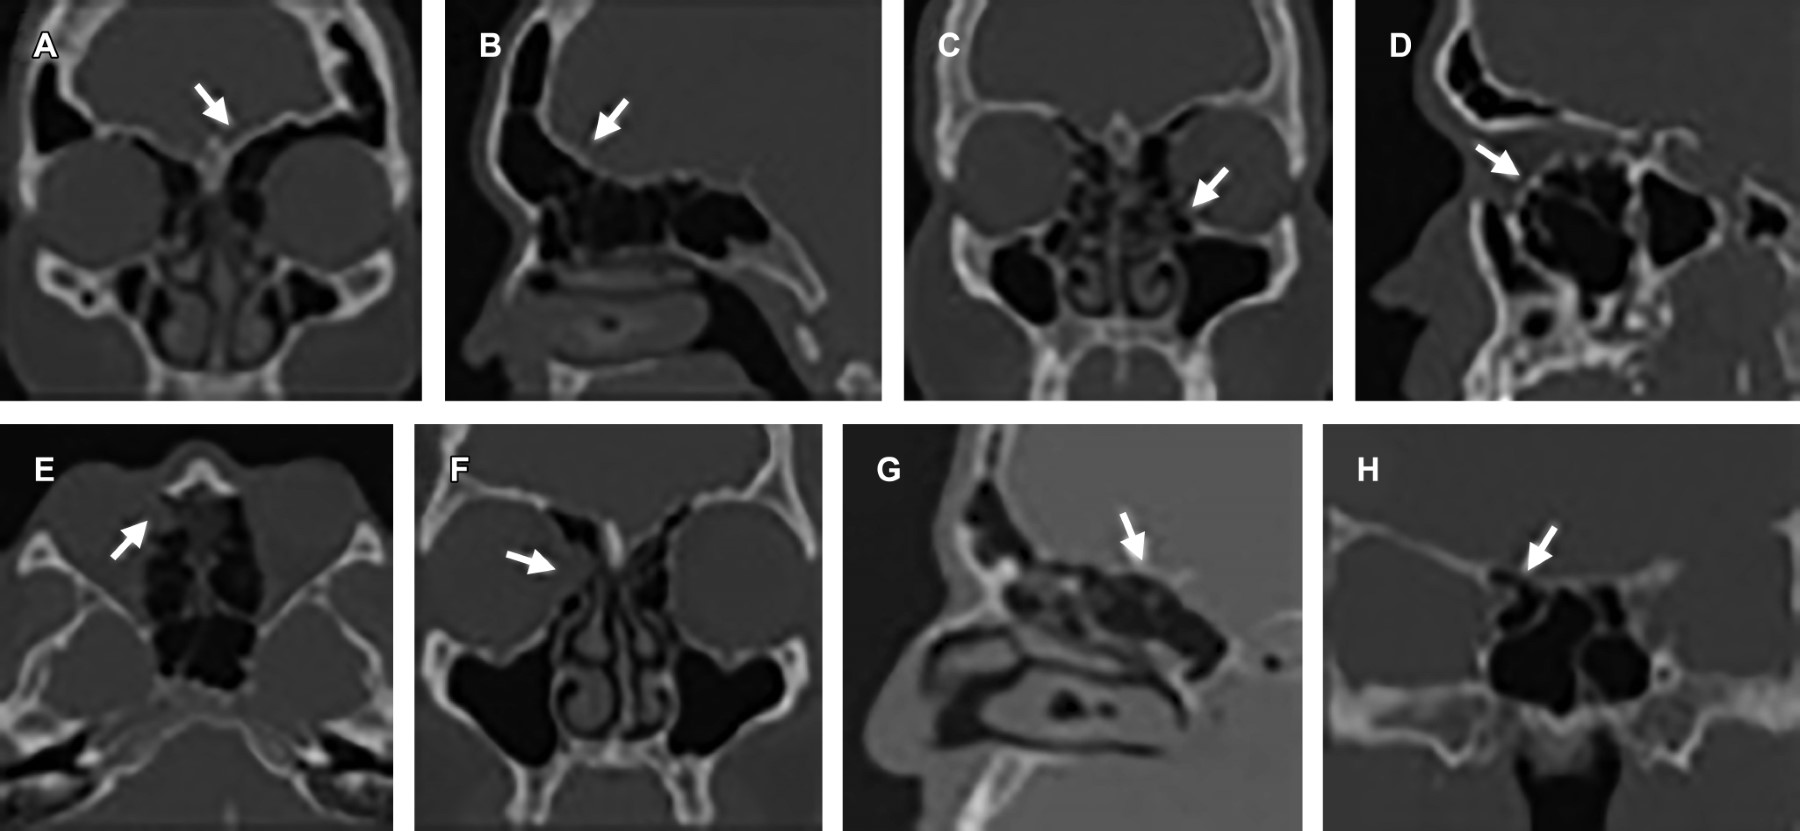

Para el patrón de neumatización del seno esfenoidal se utilizó la clasificación Hamberger donde en el tipo conchal existe una disminución en la neumatización que condiciona un margen grueso entre seno esfenoidal y silla turca, en el tipo preselar la neumatización se extiende hasta el margen anterior de la silla turca y en el tipo selar se observa una neumatización que se extiende posteroinferior a la silla turca que condiciona un margen fino respecto al clivus.2 El tipo conchal no se identificó en la muestra de estudios visualizados y el tipo selar fue el más comúnmente encontrado con 72% de estudios, el cual se asoció a dehiscencia del canal carotídeo en 1.3% y nervio óptico en 11.1% (Figura 4).

Para el patrón de neumatización del seno esfenoidal, se utilizó la clasificación de Hamberger, que utiliza los límites anatómicos de la silla turca y clivus para referir tres tipos. Conchal, margen grueso entre el seno esfenoidal y silla turca. Preselar, neumatización hasta el margen anterior de la silla turca, y selar, neumatización que se extiende inferoposterior a la silla turca y condiciona un margen delgado con el clivus. El patrón selar se identificó en 72% de los estudios, mismo que confiere riesgo de perforación y comunicación con estructuras intracraneales durante el procedimiento quirúrgico. De igual forma, este patrón de neumatización se relaciona íntimamente con dehiscencia del canal carotídeo y nervio óptico, visualizado en 1.3 y 11% respectivamente que confiere riesgo de lesión inadvertida en su trayecto.10,12